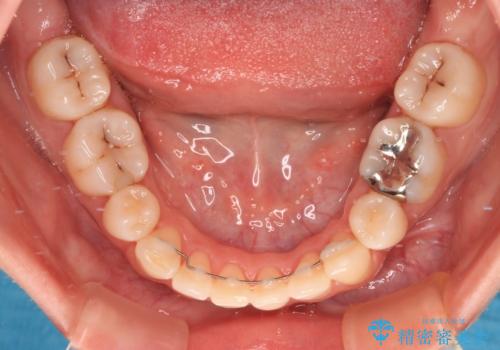

舌の突出癖の影響もあり、非抜歯矯正で治療開始したものの口元が突出し、唇が閉じにくくなってしまったため、途中で第一小臼歯4本を抜歯ししました。

口元の突出感のない、すっきりとした仕上がりとなりました。